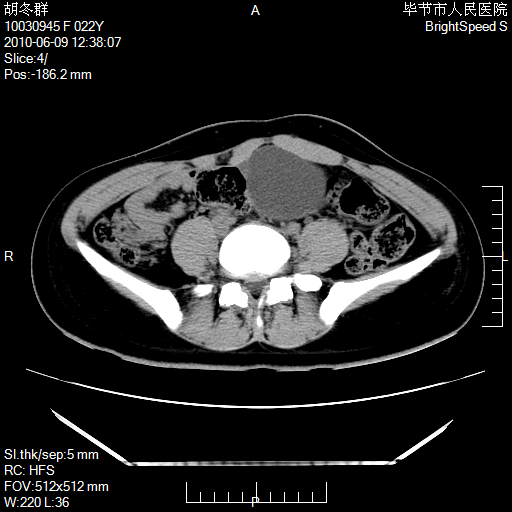

患者23岁,发现腹部包块3月。

盆腔内囊性占位;穿刺或者直接手术拿掉即可,不必紧张。

盆腔内囊性占位性病变;考虑左侧卵巢囊腺瘤。

左侧卵巢浆液性囊腺瘤。

有分隔、壁薄,支持考虑左侧卵巢囊腺瘤。排尿后,膀胱缩小,由于重力作用,肿块下移就到了膀胱位置,很好理解。